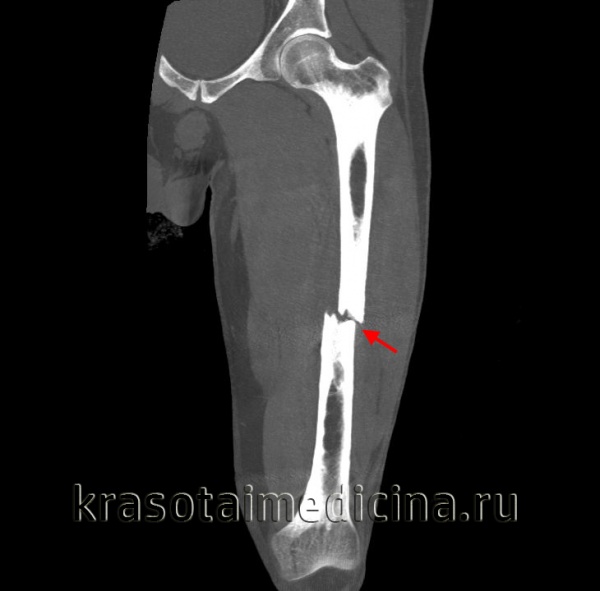

Признаки перелома головки бедренной кости

Перелом головки бедренной кости. Диагностика и лечение

Для выявления переломов этого типа достаточно, как правило, обычных рентгенограмм в прямой проекции и в проекции с наружной и внутренней ротацией бедра. Диагностике скрытых переломов часто помогают рентгенограммы в сравнительных проекциях. У всех больных с подозрением на перелом бедра должна быть тщательно изучена линия Шентона. Кроме того, при подозрении на перелом необходима оценка шеечно-диафизарного угла, который в норме составляет 120—130°. Его измеряют от точки линий пересечения, проведенных по осям диафиза и шейки бедренной кости.

Класс А: перелом головки бедренной кости

Перелом головки бедренной кости встречается редко и может проявиться в сочетании с вывихом или без какой-либо значительной деформации. Его классифицируют по двум типам на основании размера и количества фрагментов. При переломах I типа имеется один фрагмент, в то время как переломы II типа являются оскольчатыми.